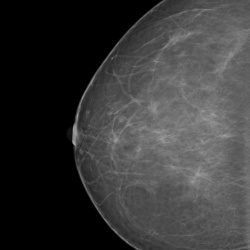

Здравствуйте, коллеги. Случай такой. В направлении на маммографию указано с-ч м/жел. Снимки представлены только левой железы, как понять? С-ч обеих желез или только правой? На границе квадрантов...